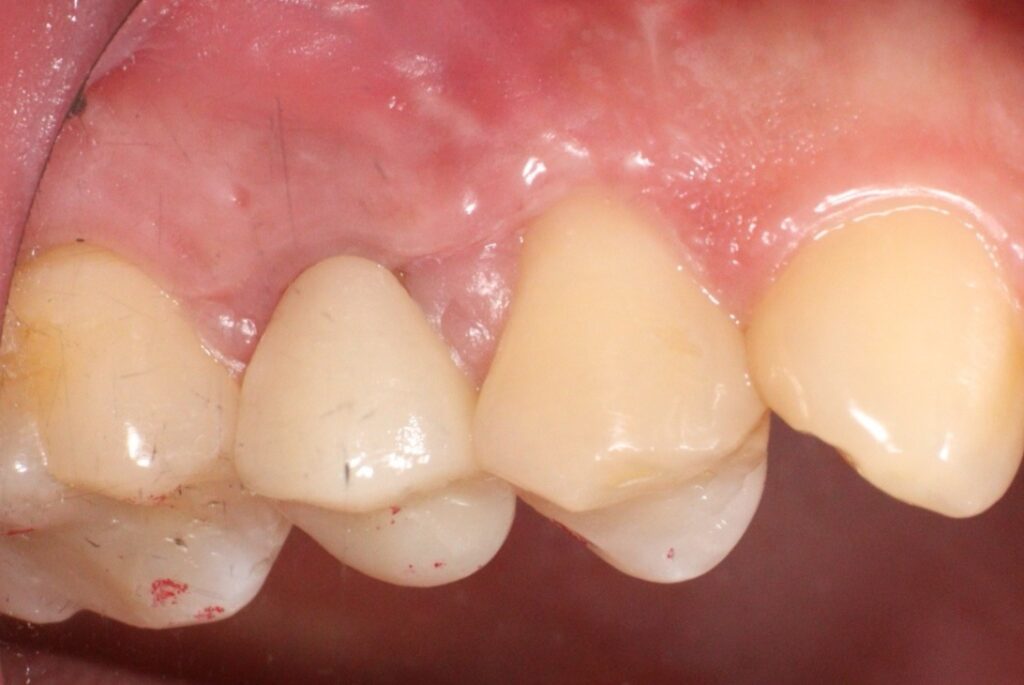

치료를 완료한 후의 모습입니다.

얼굴의 부종 감소와 눌렀을 때의

통증이 소실된 것을 확인한 뒤

최종 보철물을 시행하였습니다.

아직은 상처가 남아 있는 듯 보이는데요.